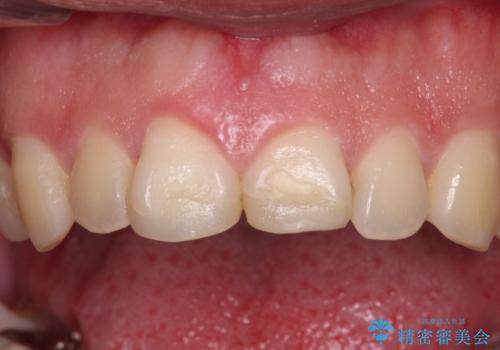

- 自転車で転んで前歯をぶつけたとのことで来院された患者様です。

事故後に受診した病院の歯科にて前歯2本の欠損した部分を修復されておりましたが、見た目が気になるとのことで、オールセラミッククラウンにて補綴治療を行うこととしました。

神経組織の状態を確認しましたが、片方は正常反応でしたが、他方は鈍い反応しかありませんでした。